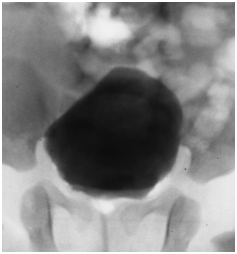

We report the case of a 28 days old girl with an antenatal diagnosis of abdominal mass. The physical examination was negative, blood sample results were within normal ranges (alpha-fetoprotein, bHCG and CA125). Urinalysis showed a small amounts of blood cells and leucocyturia, whereas the urine culture was positive for Escherichia coli (105). A micturitional cystourethrography and a complete abdominal ultrasound were performed. The micturitional cystourethrography showed a normal bladder for size and localization, with a lateral deflection of bladder imaging due to mass compression (Figure 1). The abdominal sonography showed a roundish mass with linear and exogenous margins, located in an anteromedian position compared to both the lower pole of the right kidney and the sub hepatic region. The mass was about 4x3x3 cm, and had a mixed solid -liquid echo structure (Figure 2) (Figure 3). A CT scan confirmed the presence of a 4cm cystic formation in the hepatic region but a subsequent MRI showed the mass in the right iliac fossa, and ruled out the involvement of other organs. In order to define a correct diagnosis and the subsequent surgical strategy we decided to perform a laparoscopic exploration. It was possible to identify a cystic mass in the sub-hepatic space with a diameter of 3-5cm. The mass was mobile, well delimited by the surrounding organs, with a thin long vascular pedicle (Figure 4). The exploration of the abdomen was normal and the left sided ovary and fallopian tube were normal. Although the diagnostic tests were negative, to completely rule out a neoplastic formation, the mass was totally removed through a minimal laparotomy to avoid dissemination of the fluid within the abdominal cavity in case of cyst rupture, according to the uncertain nature of che cyst. The histological diagnosis was “self amputated ovarian cyst” with necrosis and hemorrhagic fluid inside. The postoperative period was regular and the patient discharged on the second day after surgery.

Figure 3 Ultrasonography: The mass was located in an anteromedian position compared to both the lower pole of the right kidney and the subhepatic region.